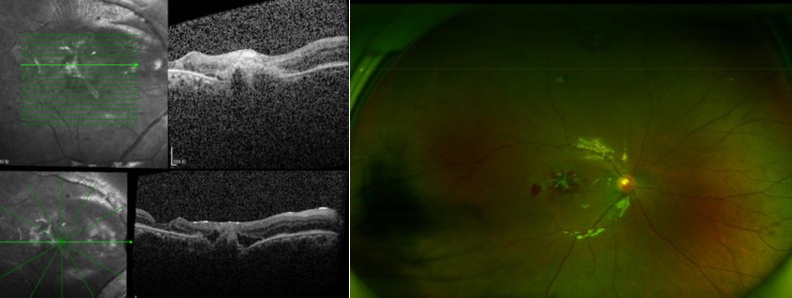

OCT显示黄斑区巨大裂孔

术后一周,张女士又一次来到眼科蒋博教授的门诊进行复查,经过一番详细检查,结果发现黄斑区的裂孔竟已开始闭合,其视力从手动提升到了0.02 。

OCT显示黄斑裂孔逐渐好转,SLO显示玻璃体积血已清除